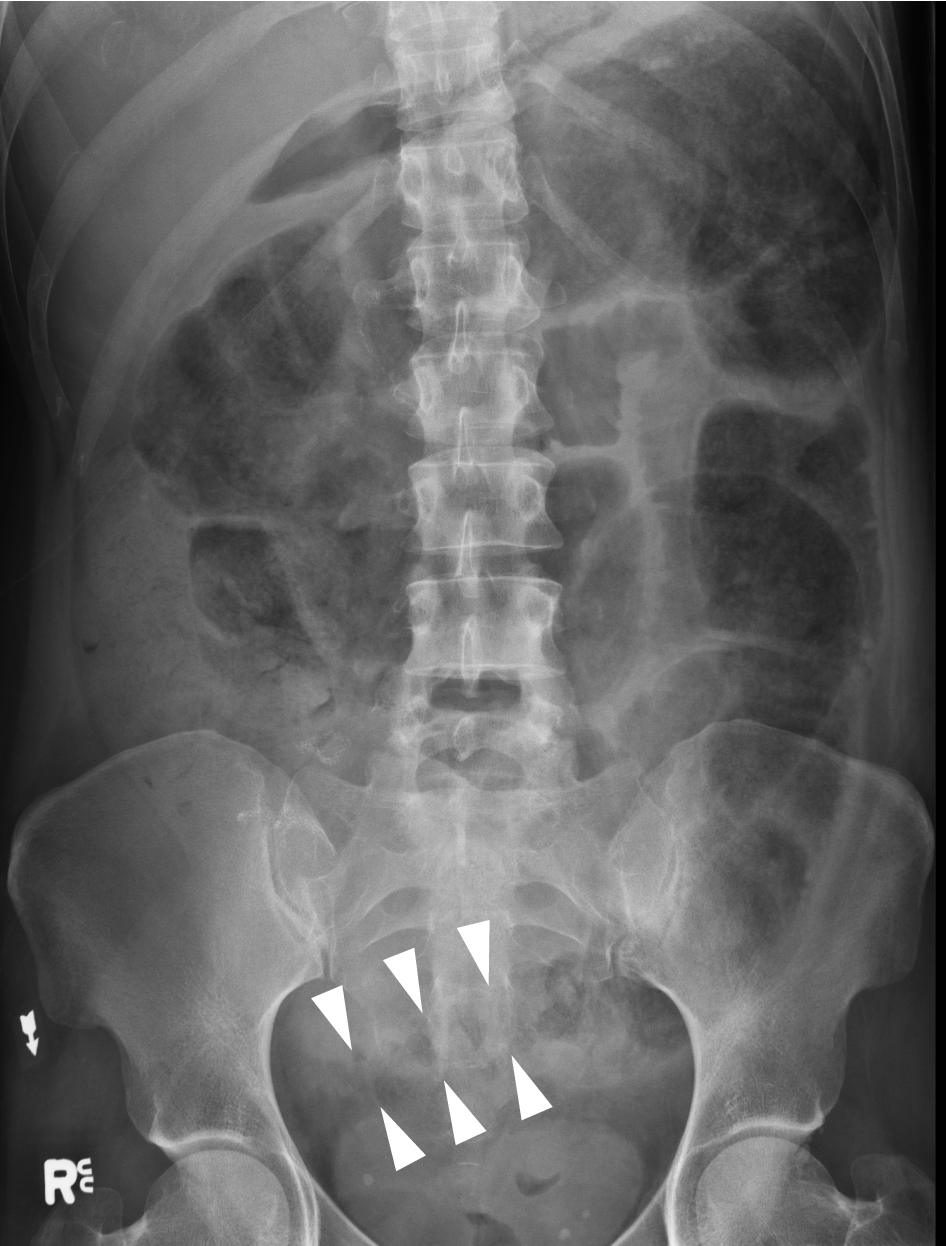

Approach to AXR Bowel gas pattern Extraluminal air Soft tissue masses Calcifications 4. This tutorial will discuss these steps. X-rays of the belly may be done to check the area for causes of abdominal pain. Typical abdominal X-ray features of small bowel obstruction include dilation of the small bowel 3cm diameter and much more prominent valvulae conniventes creating a coiled-spring appearance. Abdominal X-Ray - Small bowel obstruction - Small bowel obstruction can be identified by the dilated loops of centrally placed bowel with the venae commitantes circular bands of muscle that span the entire width of the bowel.

Because of the difference in X-ray absorption by air and soft tissues the intestinal structures intestinal air can be differentiated from their surroundings. A system for reporting an abdominal X-Ray. X-rays of the belly may be done to check the area for causes of abdominal pain. 2 Air in the abdomen Air rises to the top when there is pneumoperitoneum eg. Abdominal X-Rays Tutorial EKhalili Pouya 2018.

But as you can see from the images above you cannot reliably look for air under the diaphragm in an AXR and thus a CXR is. Typical abdominal X-ray features of small bowel obstruction include dilation of the small bowel 3cm diameter and much more prominent valvulae conniventes creating a coiled-spring appearance. Adhesions are the most common cause of small bowel obstruction in the developed world accounting for 75 of all cases. It integrated radiological images including X-ray computed tomography and magnetic resonance imaging plus clinical correlations and self-evaluation. Whether x-ray is supine or erect for fluid and gas levels correct orientation RightLeft Location of bowel small central large peripheral. A US doctor answered Learn more.